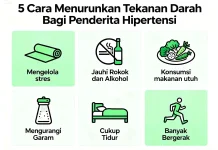

Berikut 5 Cara Menurunkan Tekanan Darah Penderita Hipertensi

- Kesehatan

- By Karno Putra.Penyiar

- 17 Jan 2026